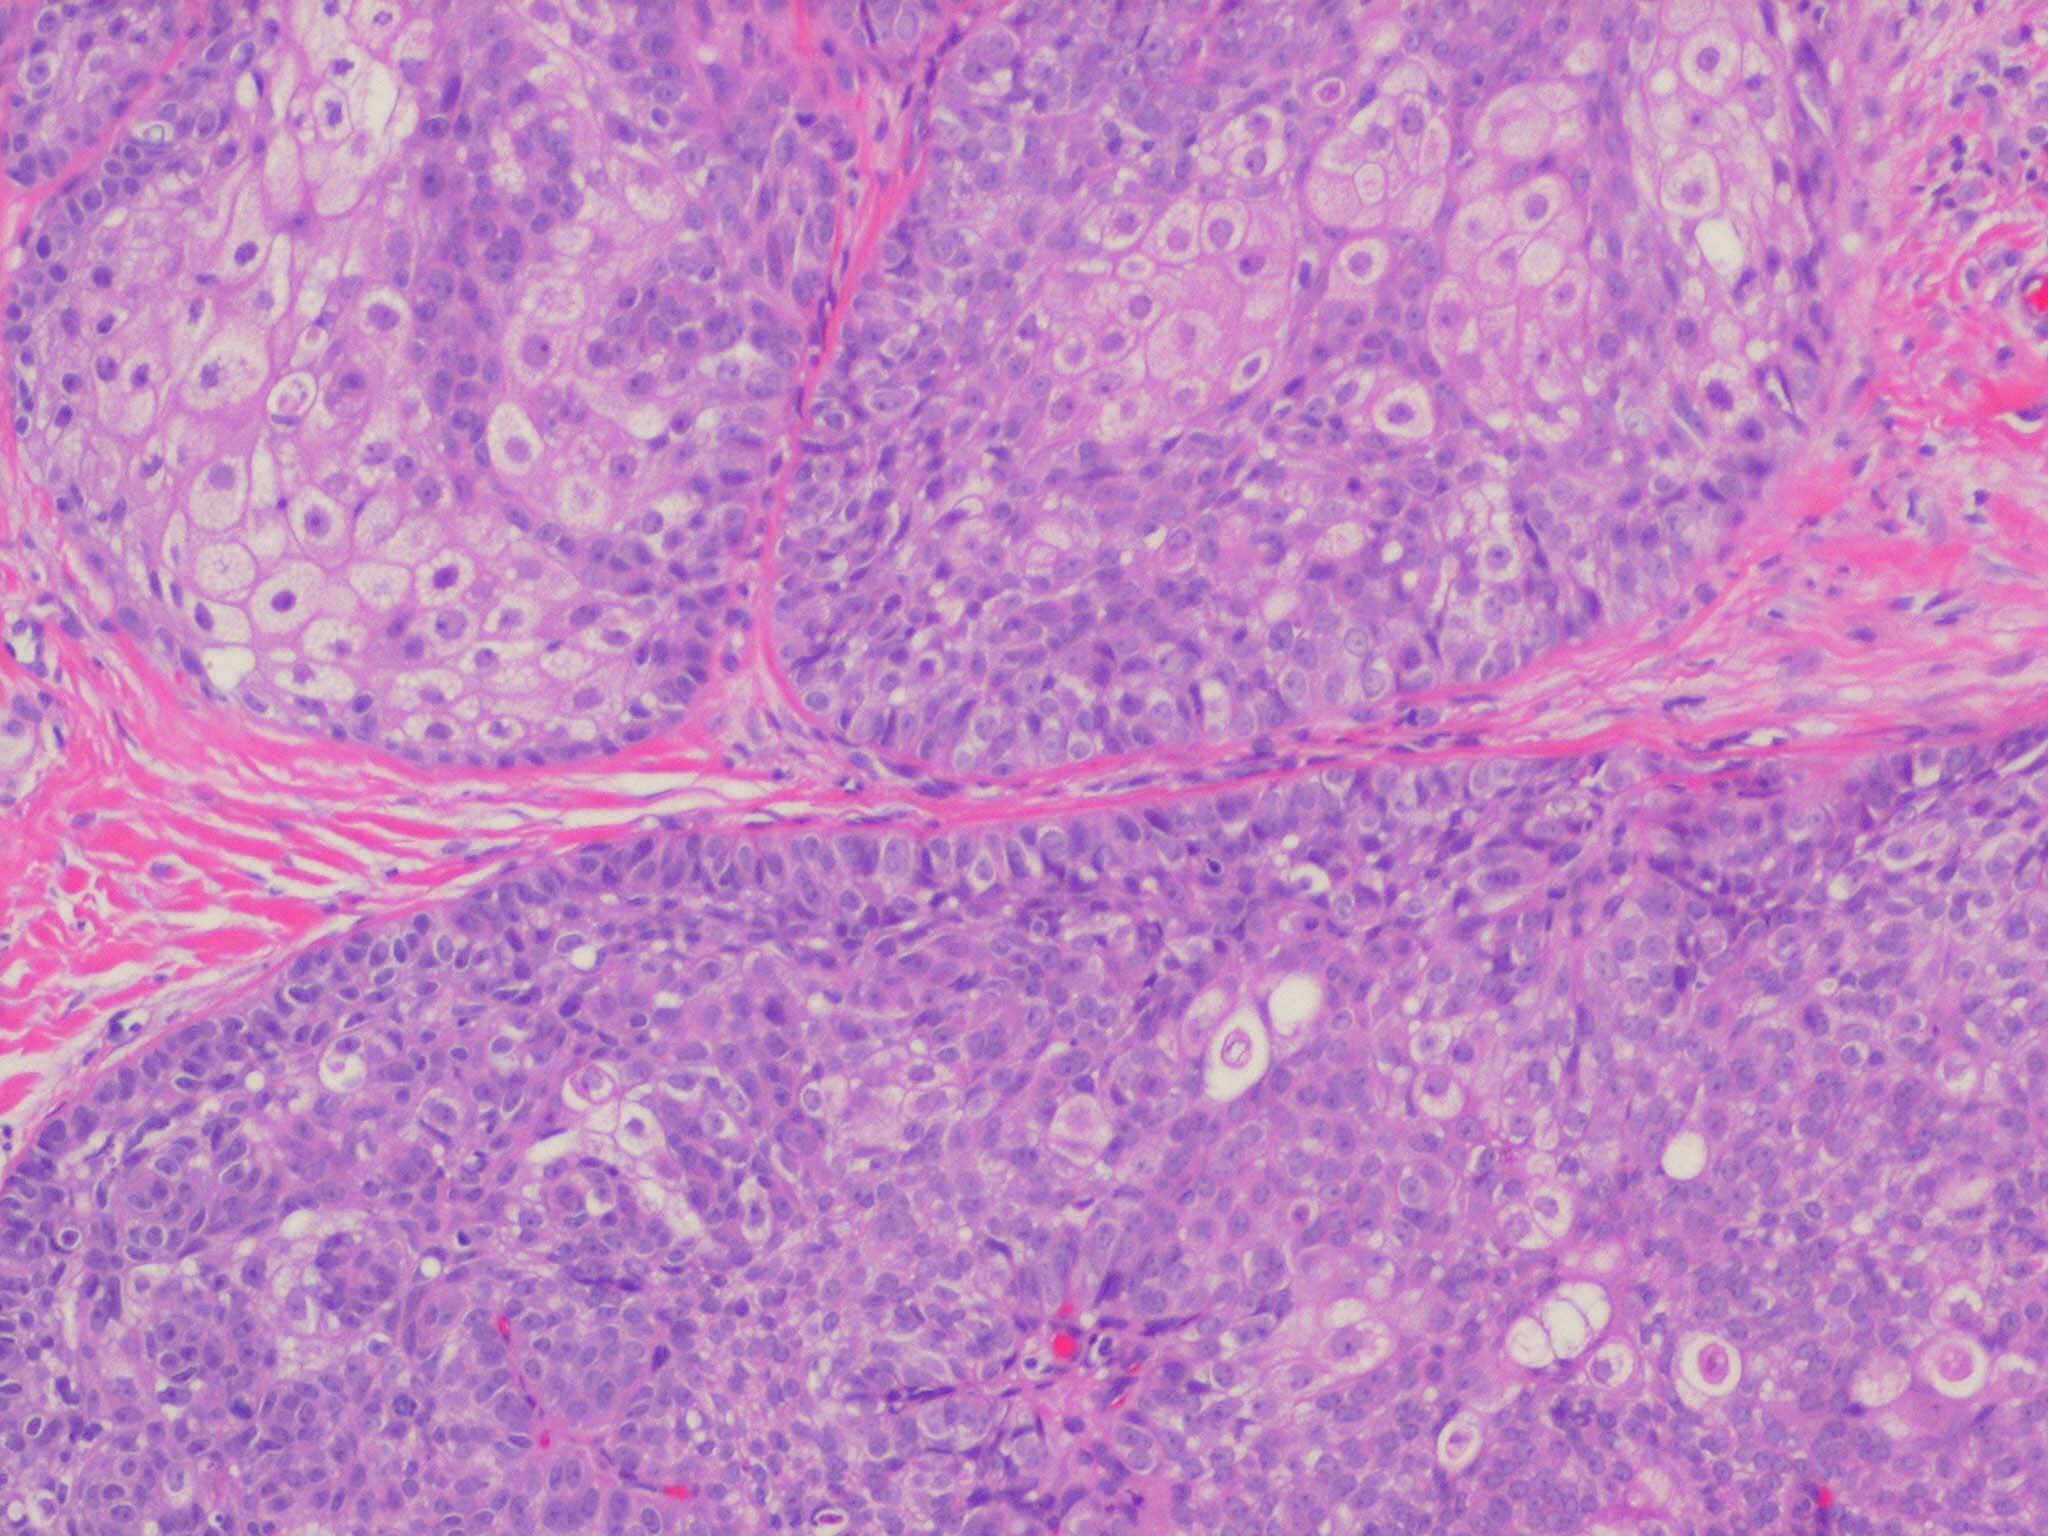

Sebaceous adenoma = غدوم دهني